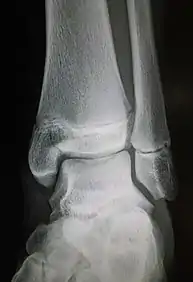

Ankle radiographs are used to detect widening of the tibiofibular syndesmosis or medial clear space. The medial clear space is the area between the talus of the ankle and the medial malleolus. Damage to the deltoid ligament and syndesmotic ligaments result in mortise instability, causing the talus to laterally shift and widen the medial clear space.[4][12] A clinical study, conducted in 2006 and published in the Journal of Bone and Joint Surgery, found that the medial clear space size of a normal ankle and an injured ankle measured at 4 millimetres and 5.4 millimetres in length respectively.[11] To confirm diagnosis, full-leg radiographs are used to inspect for fractures of the proximal fibula and widening of the interosseous clear space (or tibiofibular clear space). The interosseous clear space is the area between the medial side of the fibula and lateral side of the tibia. A peer-reviewed study, published in Injury in 2004, found that an interosseous clear space greater than 10 millimetres indicates diastasis of the syndesmotic ligaments.[4]

If necessary, Computed Tomography (CT) or Magnetic Resonance Imaging (MRI) may also be used to clarify diagnosis. MRI scans can check for interosseous membrane or tibial tubercle damage if high instability of the ankle is diagnosed.[8][11] Arthroscopy may be used to diagnose a syndesmotic lesion but is often not recommended due to operative difficulty.[13] Stress radiographs of the ankle are used to assess the integrity of the deltoid ligament and tibiofibular syndesmosis.[9][13] The size of the medial clear space can also be measured using stress radiography.[11]

X-ray, CT, or MRI scans can be used to diagnose the extent of the Maisonneuve fracture's damage and determine whether it is a simple or comminution fracture.[8] During diagnosis, a supination-external rotation pattern of injury may also be concluded if there is an isolated fracture of the posterior tubercle of the tibia.[9]